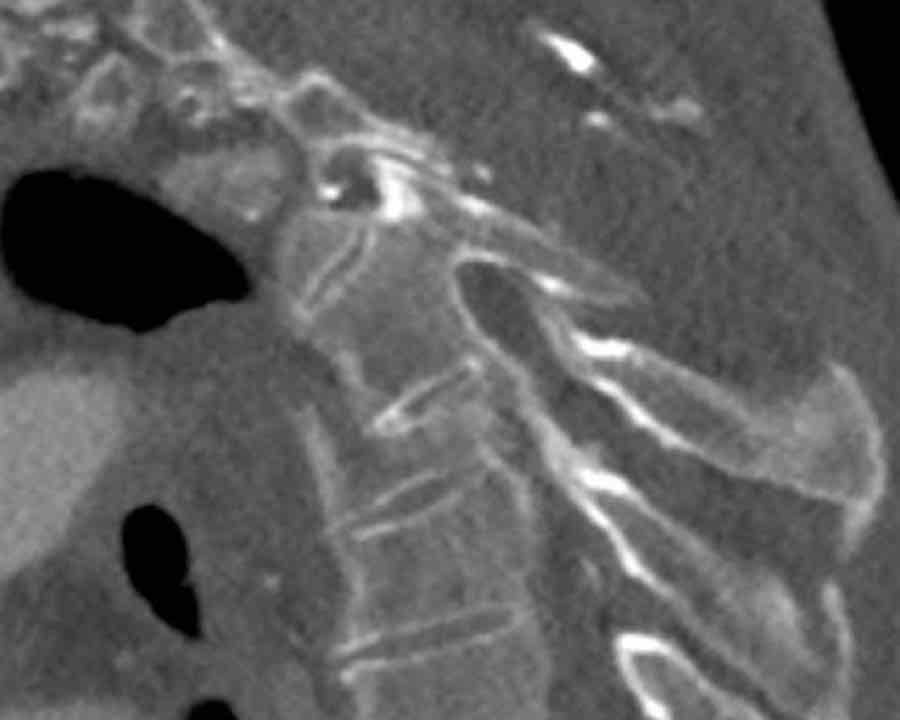

Scroll through the images

Findings:

- Perched facet joints (yellow curved arrows), so think of C injury.

- Posterior displacement of the vertebral bodies in the midline.

- Secondary A4 injury of the vertebral body.

Conclusion

Type C + A4 injury